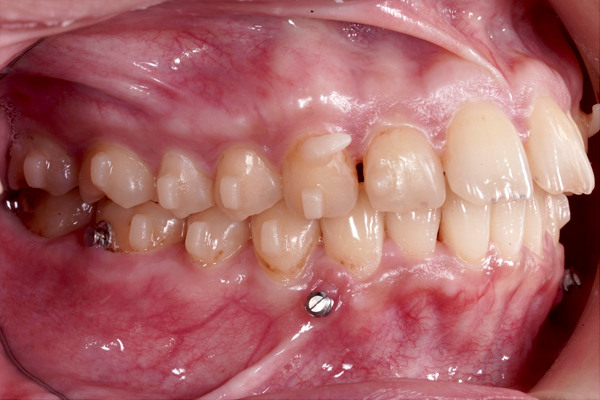

横からの比較(左側)

治療開始から9か月が経過し、前歯の重なりは徐々に改善し、上の前歯も少しずつ後方へ移動しています。見た目にも変化が現れはじめており、治療は順調に進んでいます。

本治療では、インビザラインを用いた非抜歯矯正を行っています。治療の進行にあわせて、インプラントアンカーを使用し、歯を後方へ移動させる計画です。治療期間はおよそ1年6か月を予定しており、現在は開始から9か月が経過した段階です。